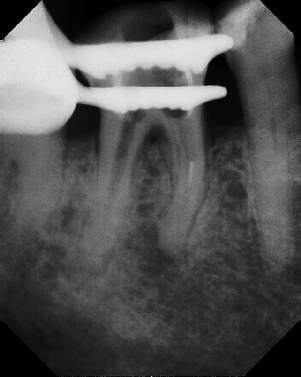

COMPLICATED ANATOMY LARGE LESIONS CALCIFIED CANALS PERFORATION / RESORPTION SEPARATED INSTRUMENTS SURGICAL CASES RETREATMENT / pOST REMOVAL OPEN APICES ACCESS THRU CROWNS Root Canal Case Portfolio

Pre-op Post-op 1 Post-op 2